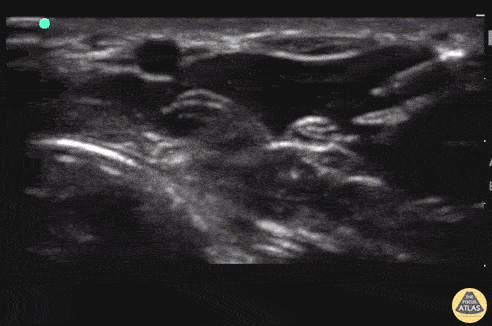

Nerve Block Gallery - Median Nerve Block

15 y/o M "fell into a mirror," landing on his hand and suffering multiple, complicated lacerations at the base of his second digit with the tendon showing. Instead of injecting local anesthesia throughout, a simple median nerve block was done under POCUS guidance. In plane technique. One stick. One happy patient. Matthew Riscinti, MD - Kings County/SUNY Downstate Emergency Medicine